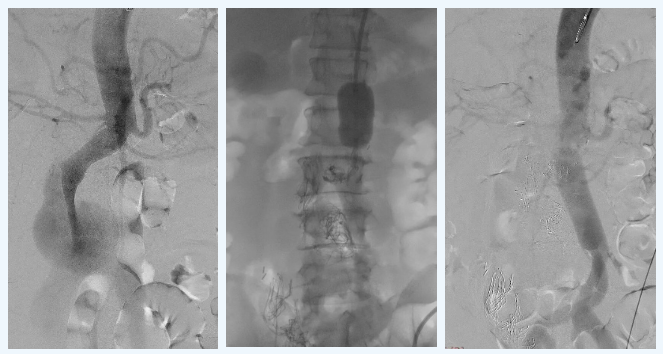

▲患者术前造影,动脉瘤最大直径达6.9厘米(左);术者用主动脉大球囊阻断腹主动脉(中);血管置换术后造影,血流恢复正常(右)

随后,团队迅速用介入球囊阻断腹主动脉上段,用阻断钳夹闭双侧髂总动脉,建立体外循环后,在动脉瘤体中找到了长达5厘米的纵行内膜破口,切除病变主动脉,替换为“Y”形人造血管。手术历时5小时成功完成,人工血管形态良好、吻合口无漏血,术中出血仅300ml。

心外科郑军主任、许尚栋主任医师团队先行术前造影,明确了赵先生为肾下型腹主动脉夹层动脉瘤及双髂动脉瘤。他们首先将主动脉大球囊顺利送至腹主动脉上段,做好大出血时的急救准备。随后打开腹腔探查,一个腹膜后的巨大血肿,犹如堰塞湖,“神奇地”暂时封堵住了主动脉的决口处,为实施手术争取了时间。但巨大血肿也将大部分脏器挤向左侧,肠道、肝、肾、动脉等全部移位,再加上腹腔内出血导致的肠系膜紫黑色,使器官辨认与病变切除难度增加。肝脏外科卢欣主任医师应邀上台,与心外科共同确认了脏器位置。